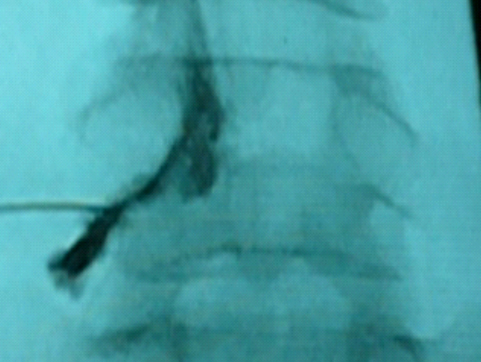

右第6頸神経根ブロック(正面像)